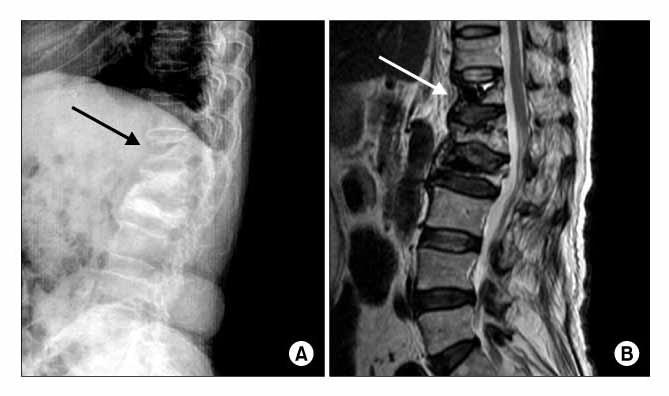

Дегенеративно-дистрофические изменения иногда приводят к редкому заболеванию — фиксирующему лигаментозу (болезнь Форестье, оссифицирующий лигаментоз). При этом заболевании патологические изменения наблюдаются в позвоночнике, чаще всего в шейном и грудном отделах. Передняя продольная связка замещается хрящевой тканью, а в некоторых случаях начинает разрушаться в области поясницы. Болезнь часто развивается на фоне хронической интоксикации, вызванной инфекциями.

Если развивается фиксирующий лигаментоз, подвижность позвоночника в пораженной области уменьшается. Пациентам становится сложно выполнять наклоны и повороты. На поздних стадиях болезни могут возникать неприятные ощущения и боли, которые затрагивают не только позвоночник, но и локти, пятки, плечи и область таза. Со временем может произойти полное обездвиживание пораженного участка позвоночного столба.

При визуальном осмотре специалист не всегда может точно определить источник болей в суставе и ограниченность его подвижности. Для диагностики заболеваний используются следующие методы:

- магнитно-резонансная томография;

- рентгенография;

- ультразвуковое исследование;

- артроскопия.

Эти методы помогают выявить изменения в связках и степень их окостенения.